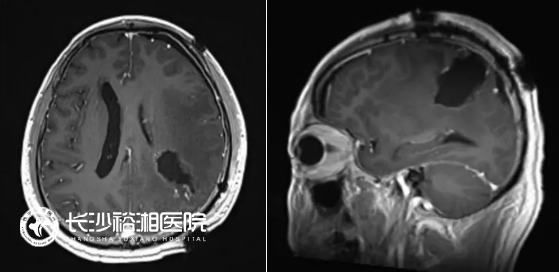

(術(shù)后48h內(nèi)MRI提示占位完全切除)